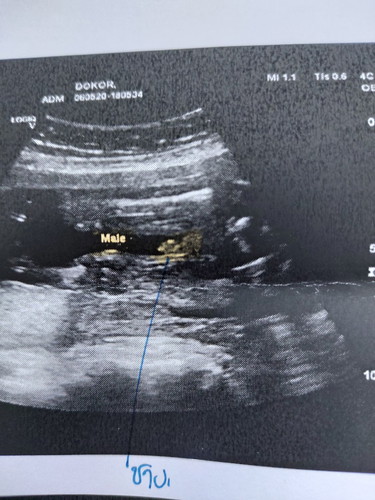

ลูกชาย

ลูกชายสมใจอิพ่อกะอิแม่แล้วจ้า23+6